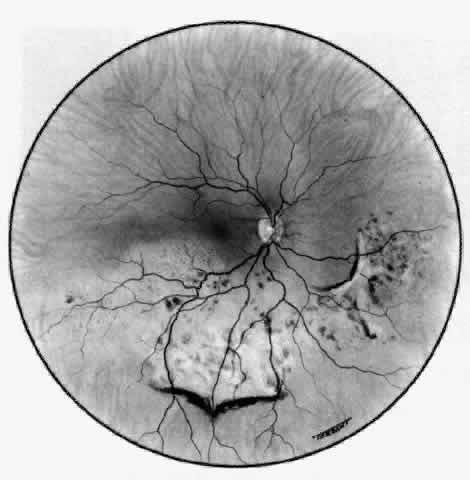

The characteristic features of necrotizing scleritis on fluorescein angiography

are hypoperfusion and, eventually, nonperfusion of the vascular

networks (Figs. 40 through 43).26 The initial changes are on the venous side of the capillary network; the

transit time of the dye increases even if the eye is red and congested. If

the disease process persists or has been present for a long time, thrombosis

and permanent vaso-occlusive changes occur. These vessels (or

the occluded capillary network) are bypassed by the opening of

anastomotic channels. New vessels in a granuloma give rise to deep intrascleral

leakage of dye (see Fig. 43). Conjunctival and episcleral involvement by the destructive change is

late but is always preceded by vaso-occlusive changes that can sometimes

Fig. 41. Late stage of fluorescein angiogram adjacent to the site of necrosis in

the same patient as in Figure 40. Although the eye is uniformly congested, the area near the necrosis shows

vascular shutdown, whereas the rest of the conjunctiva and episclera

is normally perfused. Fig. 41. Late stage of fluorescein angiogram adjacent to the site of necrosis in

the same patient as in Figure 40. Although the eye is uniformly congested, the area near the necrosis shows

vascular shutdown, whereas the rest of the conjunctiva and episclera

is normally perfused.

|

Fig. 42. Late arterial phase of fluorescein angiogram in a patient with necrotizing

scleritis. All the vessels except the main trunk and the vessels around

the limbal perforating vessels are occluded and remain unperfused

throughout the angiogram. Fig. 42. Late arterial phase of fluorescein angiogram in a patient with necrotizing

scleritis. All the vessels except the main trunk and the vessels around

the limbal perforating vessels are occluded and remain unperfused

throughout the angiogram.

|

Fig. 43. Late venous phase of angiogram of a patient with necrotizing scleritis

showing late deep leakage from vessels on the surface of the sclera and

leakage of the capillary network at the limbus and the vessels draining

it, together with poor or absent perfusion of the remaining vessels. Fig. 43. Late venous phase of angiogram of a patient with necrotizing scleritis

showing late deep leakage from vessels on the surface of the sclera and

leakage of the capillary network at the limbus and the vessels draining

it, together with poor or absent perfusion of the remaining vessels.

|